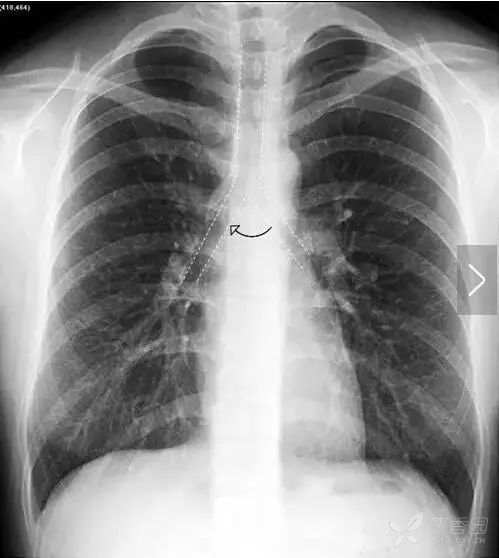

在解剖结构上,肺叶由叶间裂胸膜自然分隔而成,左肺由斜裂分为上、下2个叶,右肺由水平裂(横裂)和斜裂分上、中、下3个叶。胸部X线平片中,叶间裂胸膜和X线方向平行时可以显影,呈细线状。其中,正位胸片常可以看到右肺水平裂(图11)。

图11 右肺水平裂。正位胸片常可以看到细线状的右肺水平裂,位于右肺野中部,自肺野边缘向右肺门水平走行,水平裂以上为右肺上叶,以下为右肺中叶和下叶。